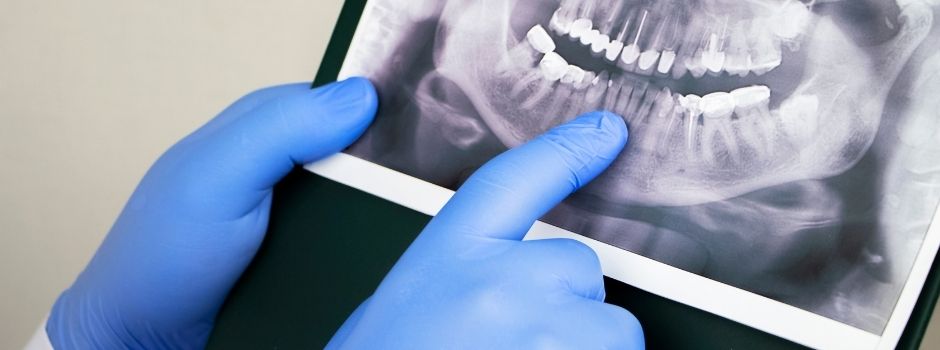

Radiografías Extraorales

Panorámicas y cefalométricas de alta definición para un diagnóstico confiable.